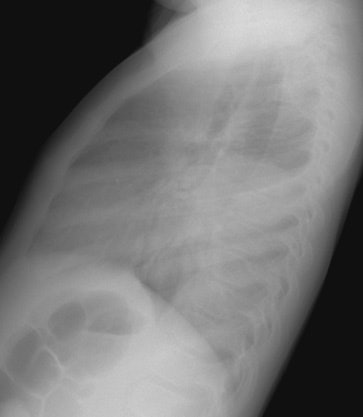

The CXR demonstrates a large left lung mass. The patient was initially felt to have a pneumonia, but subtle rib destruction can be seen involving the left posterior ninth rib. When the radiographic findings did not improve a CT scan was performed (See below). (Click images to enlarge)